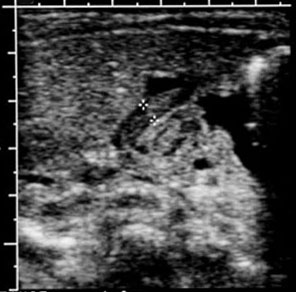

Pediatric Radiology > Abdominal > Upper GI > Hypertrophic Pyloric Stenosis - Sonographic Features

Hypertrophic Pyloric Stenosis - Sonographic Features

Hypoechoic ring of hypertrophic pyloric muscle around echogenic mucosa

centrally on cross section |